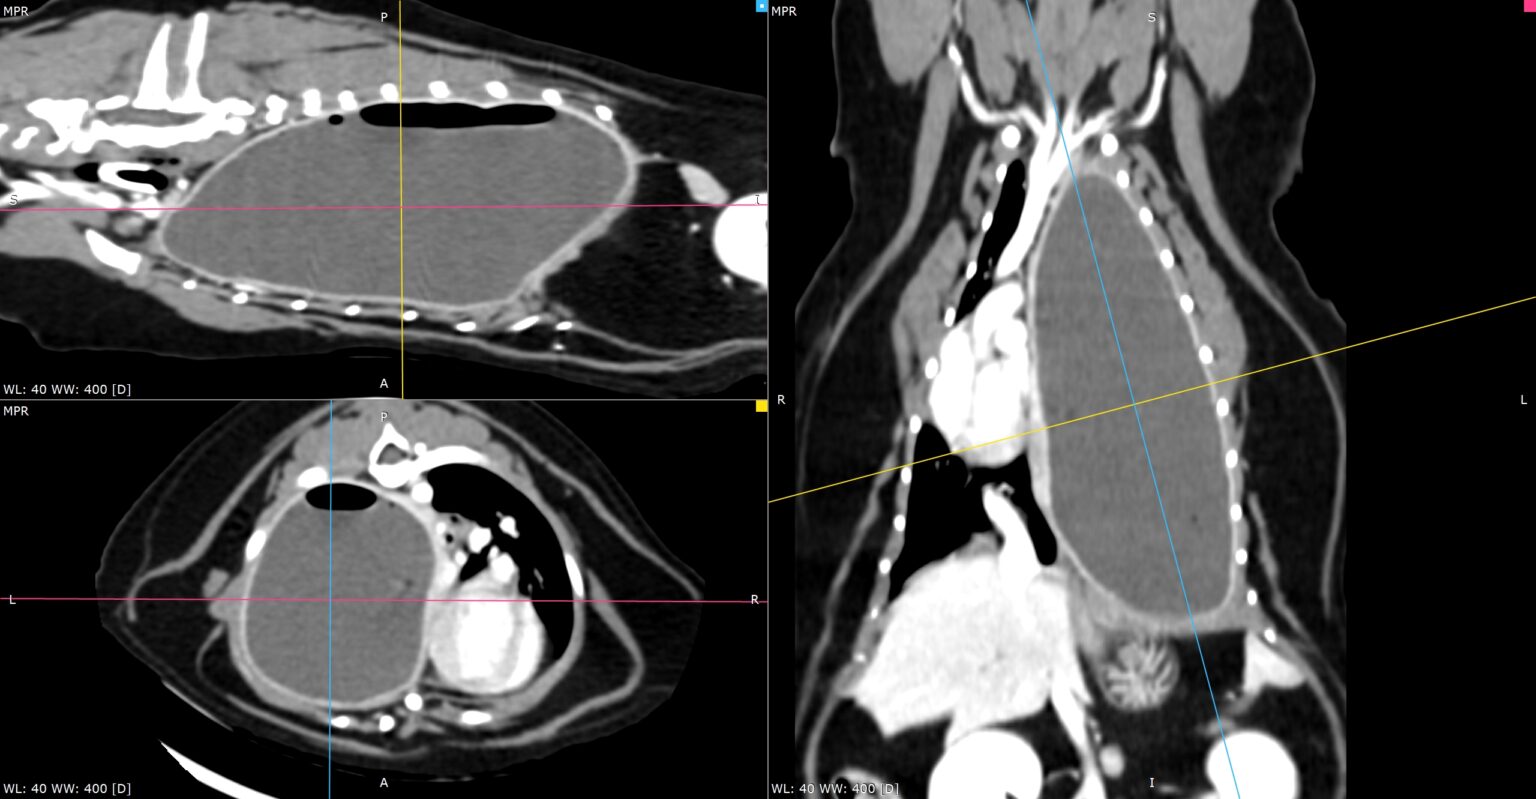

Scanner thoracique en reconstruction multiplanaire (MPR) illustrant un sarcome costal chez un chien.

Les reconstructions dans les trois plans mettent en évidence une masse tumorale infiltrante développée à partir des côtes gauches, avec atteinte des tissus mous adjacents et déformation locale de la paroi thoracique, comme indiqué par les flèches. Ce type d’imagerie permet une caractérisation précise de l’extension osseuse et extra-osseuse de la tumeur, indispensable à la planification d’une chirurgie oncologique large et raisonnée.